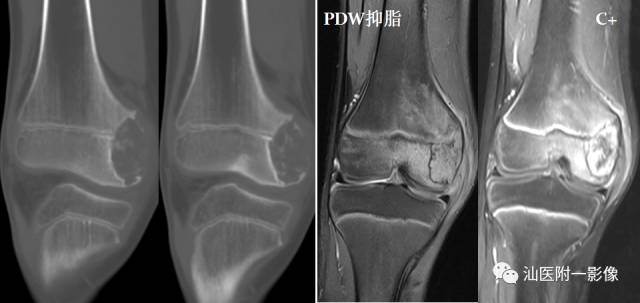

•软骨母细胞瘤为来源于幼稚软骨细胞(软骨母细胞)。

•常见于青少年,多发生于10~20岁之间。

•多发生于四肢长骨,以胫骨、股骨和肱骨多见。

•软骨母细胞瘤的溶骨区常常开始位于骨骺,倾向于越过骨骺线,向干骺端蔓延。